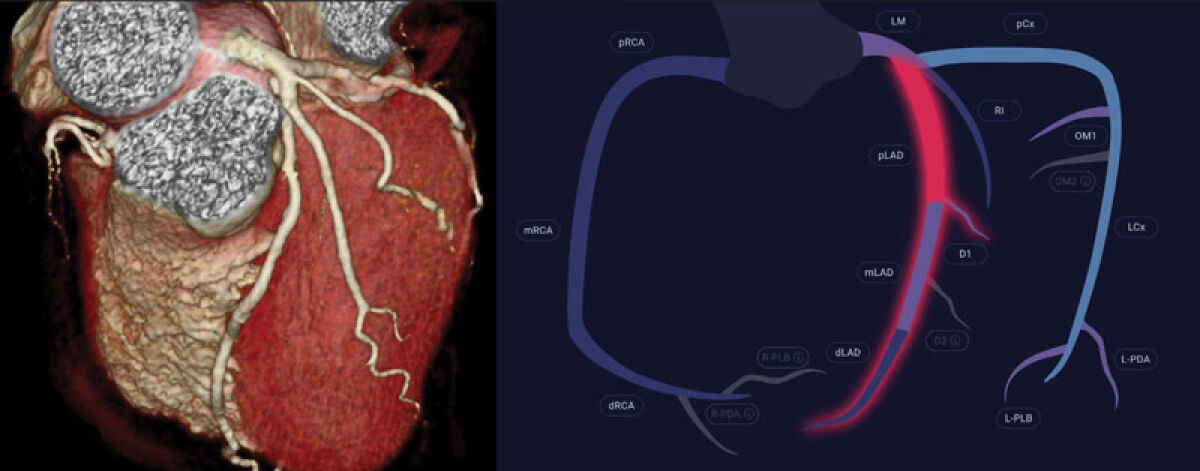

RMC recently became the first facility in Michigan to integrate a groundbreaking AI platform for diagnosing heart disease. “We’ve always been early adopters,” Dr. Atallah said. “Decades ago, we brought the first cardiac catheterization lab to Rochester and 3D CT angiography (3D Heart Scan) to Michigan. Adopting AI continues that tradition of combining innovation with compassionate care.”

“The pure benefit for patients is that we can now save lives with one simple scan,” he added. “One CT scan shows us if there’s disease, where it is and how it’s impacting the heart. Waiting for a cardiac event makes no sense—you’re already too late. A 3D Heart Scan identifies tomorrow’s heart attack, today.”

The technology’s power was proven just weeks after its launch. A patient arrived with mild symptoms that might not have raised alarms elsewhere. The new AI system analyzed the data within seconds, flagging a critical blockage in the left anterior descending (LAD) artery, referred to as the “widow-maker” due to its lethal potential.

An angiogram confirmed a 90 percent blockage posing an imminent risk of a fatal heart attack. The team placed a stent and restored blood flow, preventing what could have been a deadly event—marking the first time in Michigan that an AI-driven diagnosis directly saved a life.